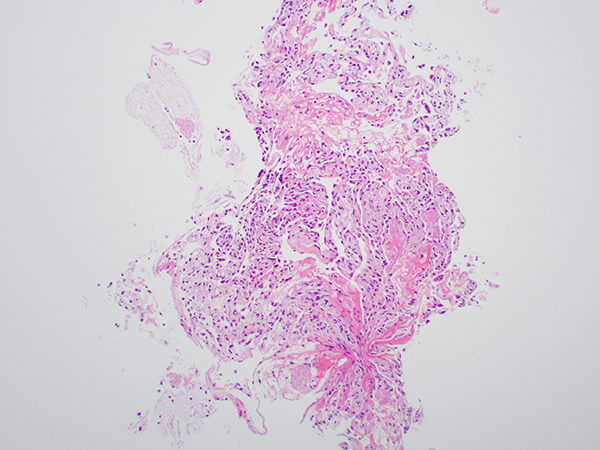

Clinical History: A 35-year-old man with a history of smoking and HIV infection presents with dry cough, fever with sweats, and difficulty in breathing for several days. Clinical examination reveals an increased respiratory rate, tachycardia, and fine crackles on auscultation of the chest. Chest radiograph shows diffuse bilateral infiltrates and subsequent high resolution computed tomography shows multiple ground glass opacities in the lung. Bronchoalveolar lavage (BAL) and transbronchial biopsy (Figure 1-3) are performed. Tissue is also sent for bacterial, fungal and mycobacterial cultures

Primary exposure to Pneumocystis occurs early in life; organisms remain in the latent form and are reactivated in an immunocompromised host. Four developmental forms of Pneumocystis are described: trophozoites, precysts, sporozoites, and mature cysts. Through cell wall thickening, the trophozoites develop into precysts, and then, through meiosis and mitosis, sporozoites are formed. Mature cysts contain multiple sporozoites. The cysts are the forms can be seen in tissue sections, are 5-7 µm in size, and are round-to-oval, crescent-shaped, disk-shaped, or boat-shaped organisms identified readily by GMS and PAS stains. The typical features of pneumocystis pneumonia consist of chronic interstitial inflammation and frothy eosinophilic exudates. Rarely, pneumocystis pneumonia presents as granulomatous inflammation in patients who are marginally immunocompromised. Granulomas are loose to well-formed and can be with or without necrosis.